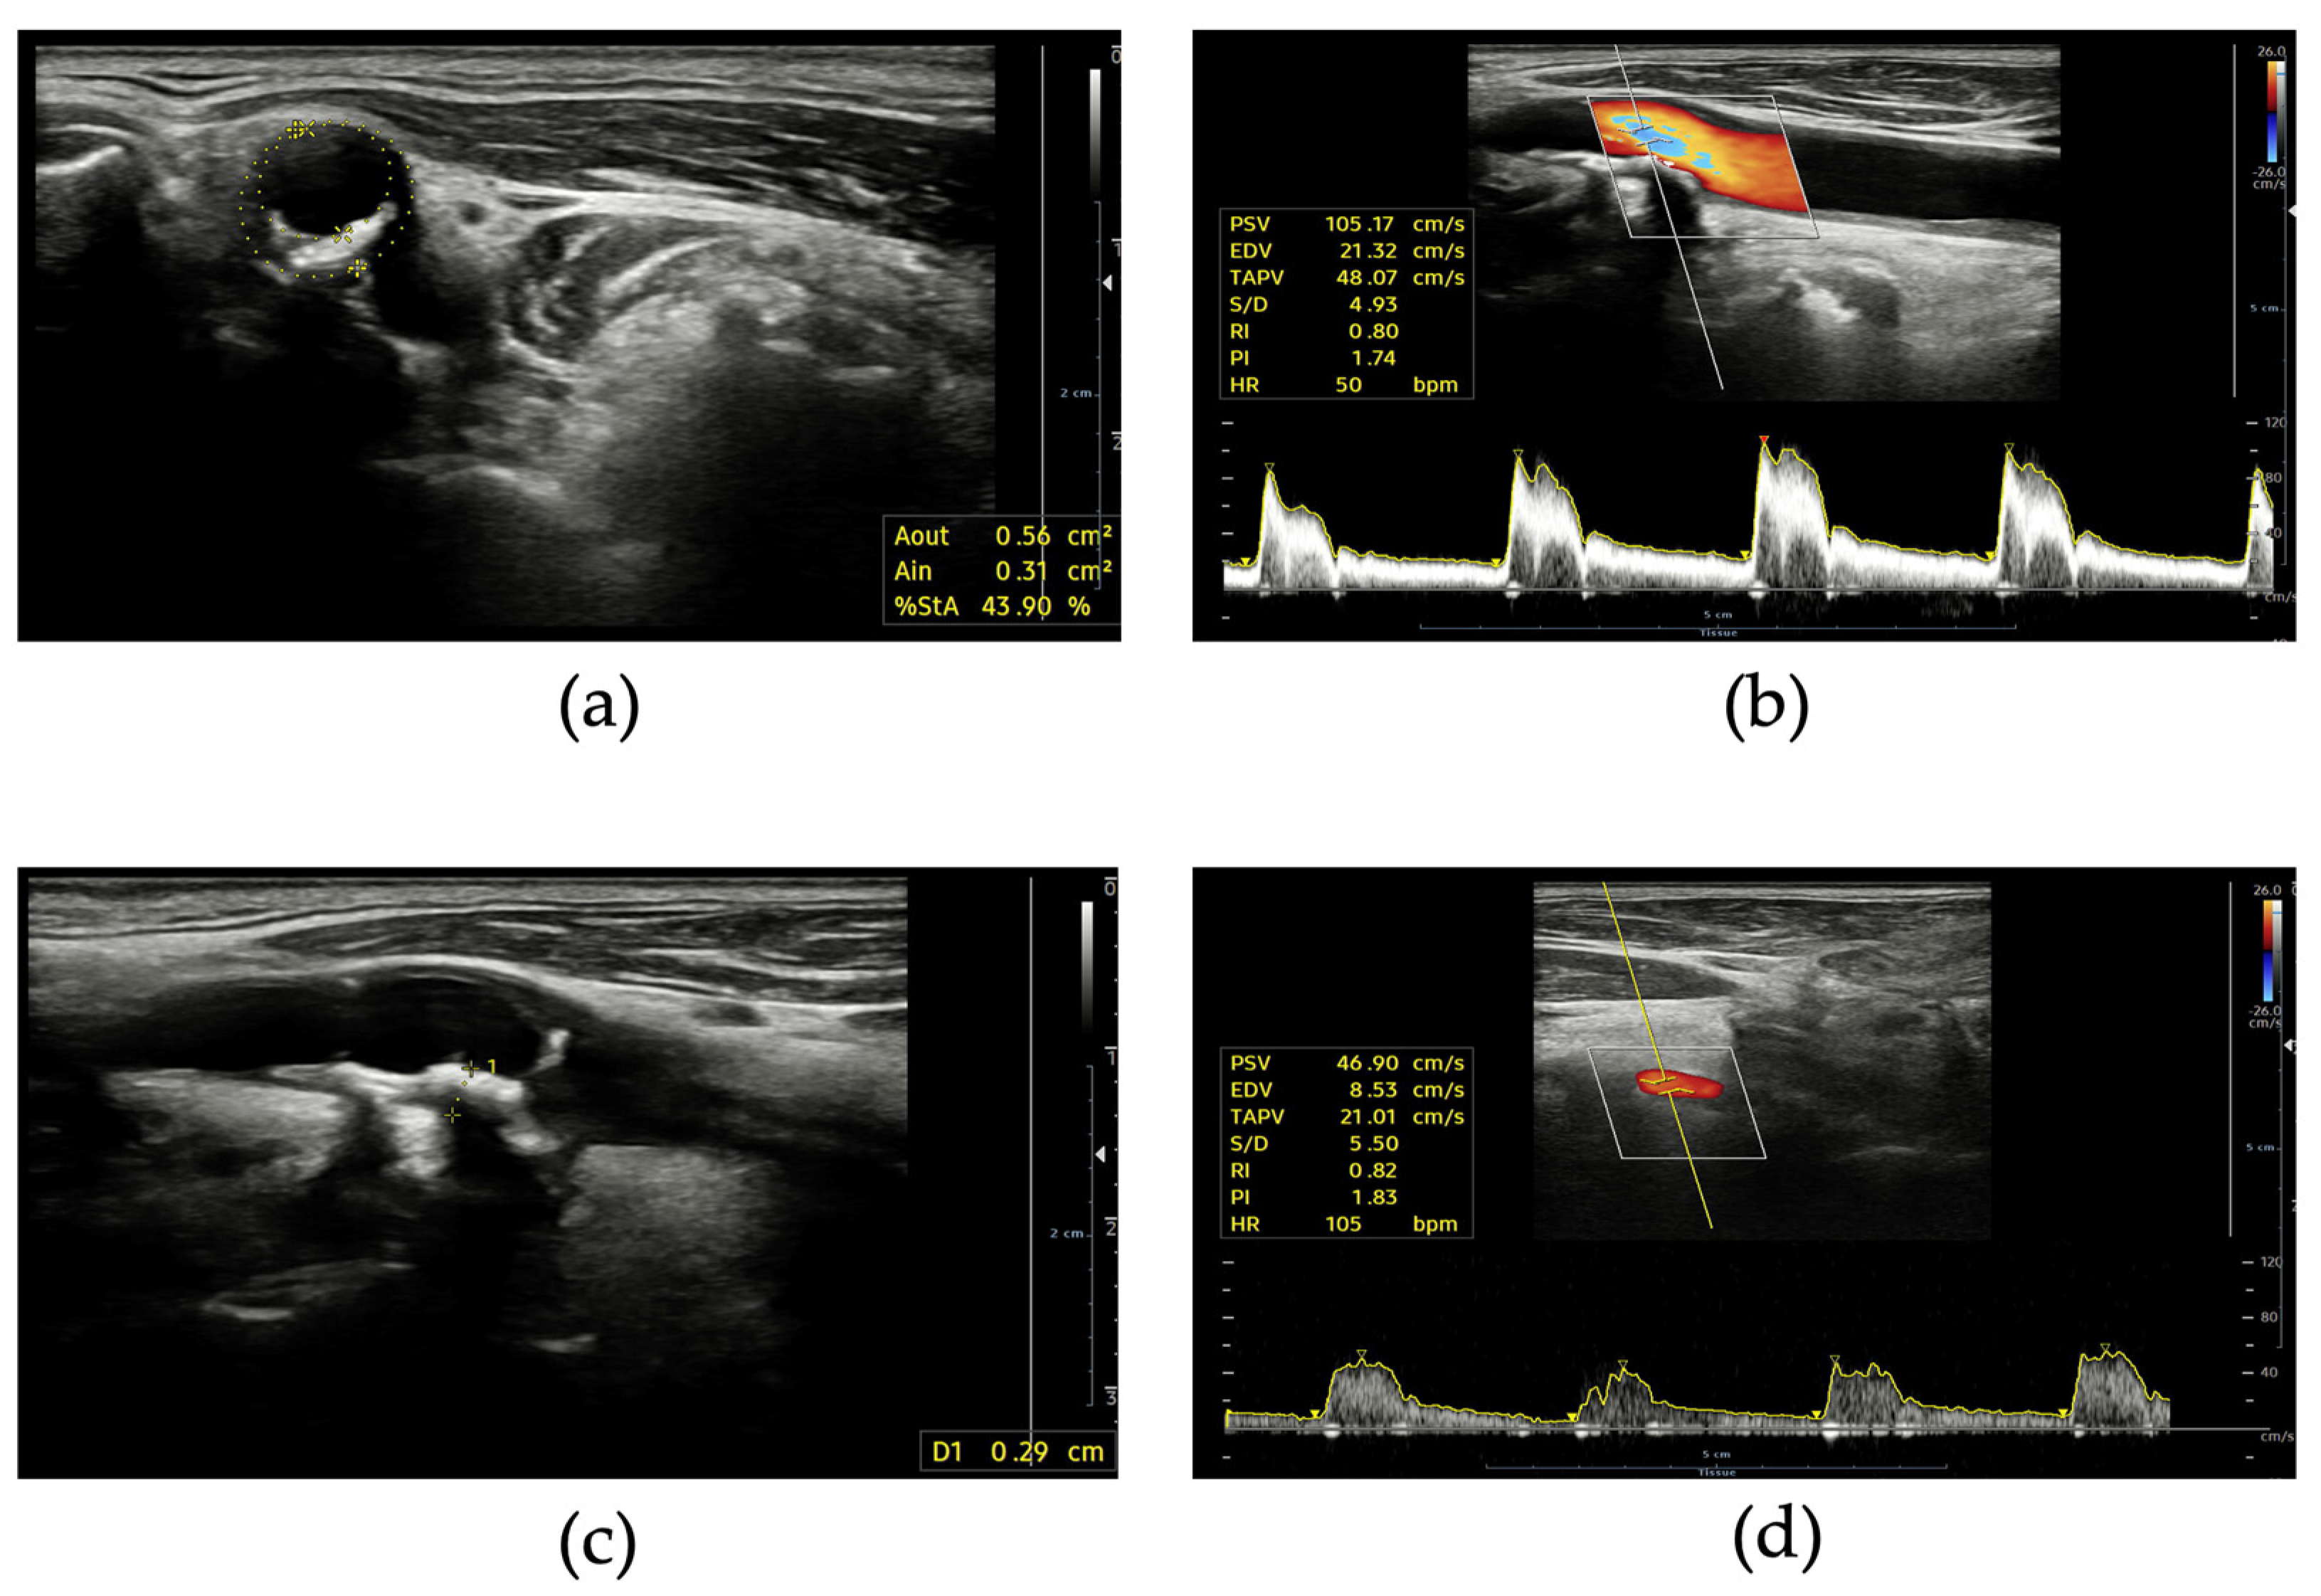

4. Supra-Aortic Trunks Ultrasound in Cardiovascular Prevention